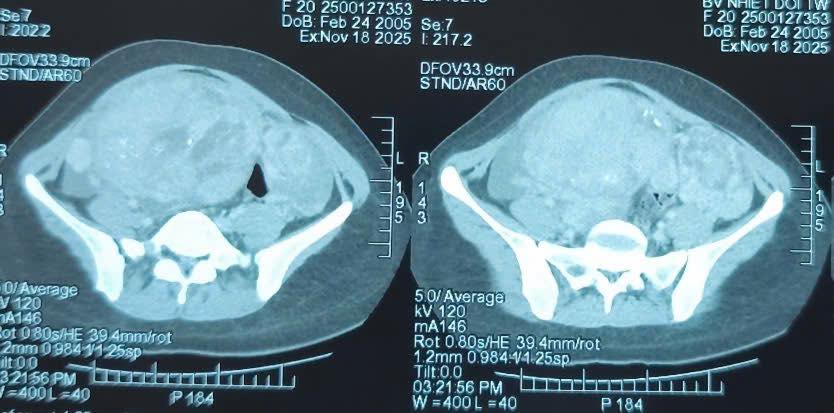

Khám lâm sàng ghi nhận một khối bất thường lớn vùng hạ vị. Hình ảnh chụp cắt lớp vi tính cho thấy khối u vùng hạ vị kích thước 110x163x244 mm, bờ không đều, bên trong có nốt vôi hóa và dịch tự do ổ bụng. Bệnh nhân được chỉ định phẫu thuật cắt bỏ khối u.